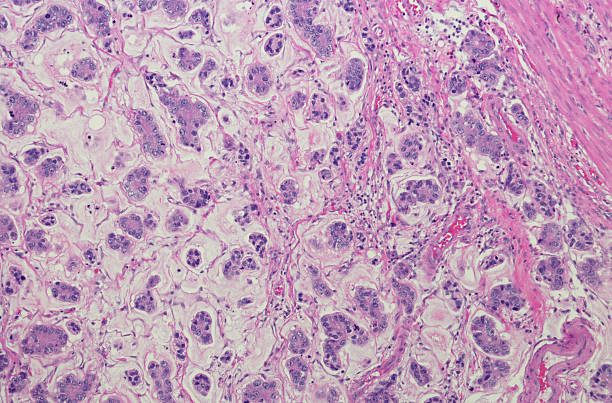

위암은 많은 사람들에게 알려져 있지만 무증상으로 진단되기 때문에 조기 발견이 중요합니다.

✅위암 초기증상 4가지 꼭 확인!

위암은 조기 발견이 생존율을 크게 높일 수 있는 질환입니다.